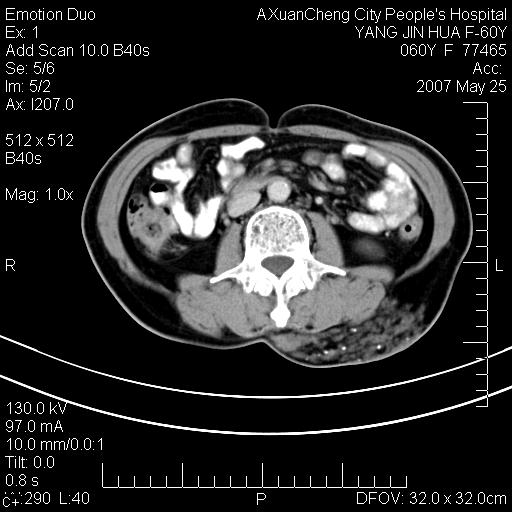

发现左侧腰背部包块40余年,逐渐长大,质软,局部表面可见扩张的血管影

左背部皮下良性肿瘤,密度不均,边界不清,内有脂肪、钙化,增强扫描无明显强化,血管平滑肌脂肪瘤?进一步诊断有困难,建议穿刺活检。

左侧背部皮下混杂密度肿块,结构较疏松,边缘欠光整,内有多发斑点状钙化,考虑:皮下血管瘤。

这个病理增强扫描之前,我们是考虑是血管瘤,可是现在增强后一点强化都没有,还能考虑是血管瘤吗

其内可见斑点状静脉石,血管瘤有时就不增强化,还是血管瘤。

1、病灶内有小点状钙化,静脉石?这可是血管瘤诊断的重要征象

2、病灶内有脂肪组织增生,血管瘤有此特点